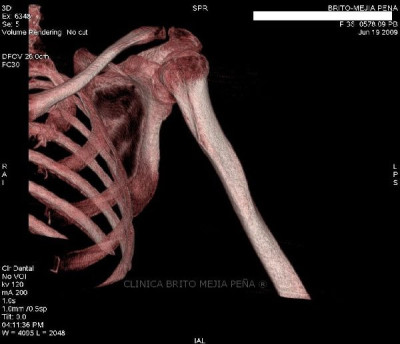

Húmero normal